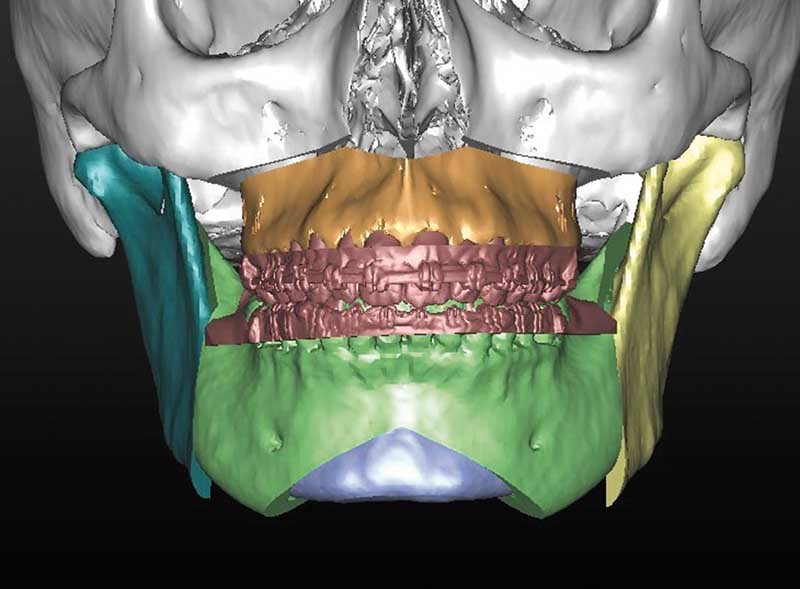

– élaboration des images 3D en isolant des différents constituants anatomiques : crâne et maxillaire, mandibule, dents, dispositifs d’orthodontie, implants endo-osseux et prothèses conjointes éventuelles, etc.

L’enregistrement des classiques modèles en plâtre (en occlusion corrigée de Classe 1) à l’aide d’un scanner conventionnel (format DICOM) ou par empreinte optique (format STL) est ensuite intégré au squelette dento-squelettique ; étape désignée « matching des modèles ».